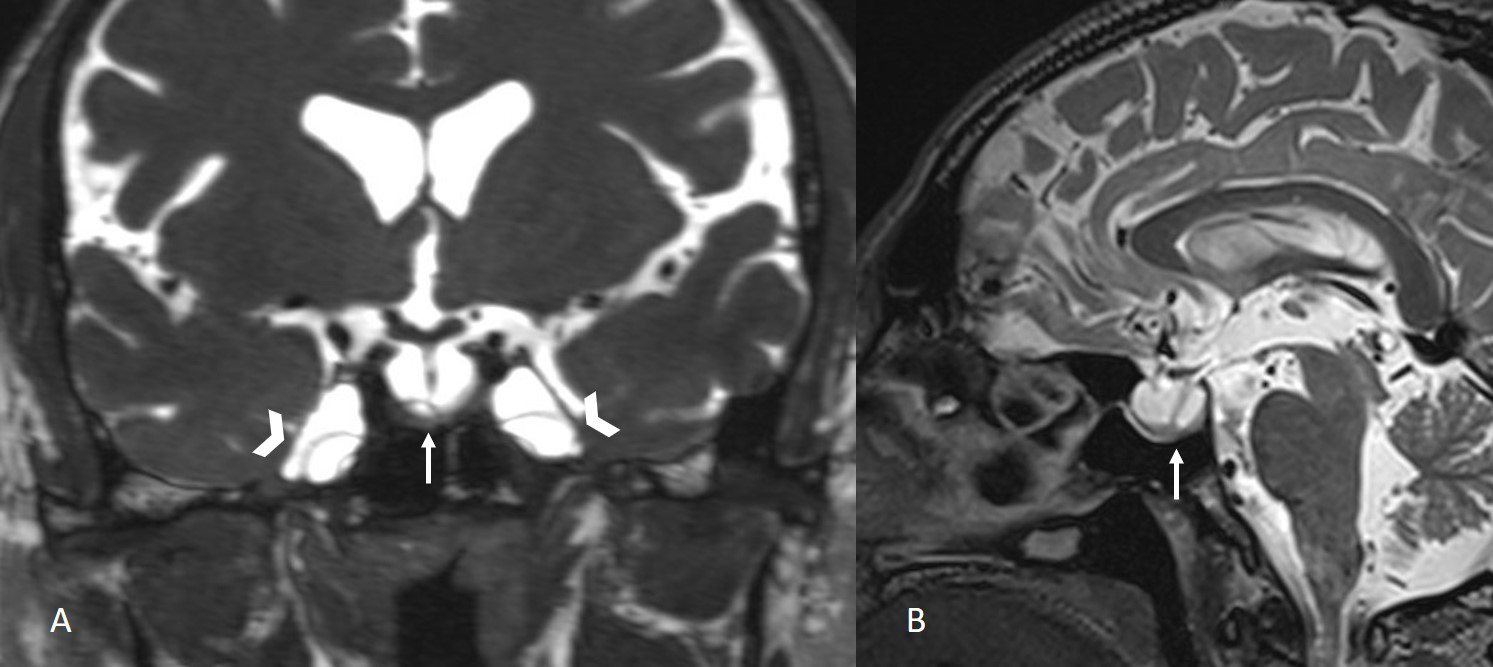

The institutional review board approved this single-center retrospective study. Patients with suspected CSF leakage who underwent MRI with a special protocol between 2012 and 2023 were evaluated. Images of 240 consecutive patients were assessed for CSF leakage by two neuroradiologist with 10 and 3 years of experience. Patients with leakage from sites other than the sphenoid sinus were excluded from the study (n = 220). Six out of 20 patients with a history of trauma or surgery of the sphenoid sinüs or cavernous sinus were also excluded. The remaining 14 patients with sphenoid sinüs CSF leakage formed the study group. Leakage was supported by surgical findings and beta-2 transferrin test. All imaging was performed using 3 Tesla (Verio, Siemens, Erlangen, Germany) or 1.5 Tesla (Aera, Siemens, Erlangen, Germany) MR scanners. The MRI protocol for CSF leakage consisted of T2 weighted fat suppressed coronal plane images with 3 mm slice thickness, T2-weighted sagittal plane SPACE images with 1 mm slice thickness, and CISS coronal plane images with 1 mm slice thickness. All images were evaluated by two radiologist with 4 years of experience in terms of empty sella, enlargement of the Meckel's caves (Figure 1), fluid in the optic nerve sheaths, vertical tortuosity of the optic nerves (Figure 2), arachnoid pits, encephaloceles (Figure 3), and lateral recess pneumatization of the sphenoid sinuses. Lateral recess pneumatization was defined as pneumatization lateral to the line connecting the foramen rotundum and the Vidian canal (Figure 4). The side of the leakage and the other accompanying sites of leakage were noted. The presence of a bony defect was evaluated on CT images (Figure 5).Descriptive statistics were used for data analysis. Continuous variables were presented as mean ± standard deviation [median (minimum?maximum)], and categorical variables were expressed as frequency and percentage.

Figure 1: Coronal CISS image and sagittal T2-weighted SPACE image show empty sella (arrows) and enlargement of the Meckel's caves (arrowheads). |